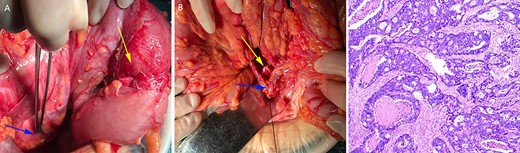

After sufficient preoperative preparation and discussion, we decided to perform open radical resection of colon cancer operation for the patient. During surgery, we found that the tumor was located in the lower part of the descending colon (in the right abdominal cavity), the size of the tumor was ~4.0 x 5.0 cm in diameter, the boundary between the tumor and the surrounding tissue was clear and the tumor invaded the whole intestinal wall. Moreover, the patient’s the left ovarian vessels were significantly thickened, especially the veins (Fig. 3A), and the inferior mesenteric vessels were absent (Fig. 3B). The operation time was 115 min and intraoperative blood loss was 33 ml. Histological examination of the resected specimens revealed a moderately differentiated carcinoma (Fig. 3C). On postoperative Day 1, the laboratory examination showed that white blood cell count was 13 600/mm3, and neutrophil cell count was 12 300/mm3. These results showed that the leukocytes and neutrophils were significantly increased, and antibiotics were applied to prevent the occurrence of infection in consideration of aseptic inflammatory reaction in the operation area and systemic stress reaction. There was no obvious abdominal pain, chills, fever and other discomfort in the patient after operation. The drainage tube outflow was a pale red liquid (~50 ml/day). The anal exhaust time was on postoperative Day 3 and the patient started a fluid diet. However, on postoperative Day 5, the peritoneal drainage volume had increased to ~500 ml/day and the liquid had become pale yellow, which was confirmed as lymphatic leakage by Sudan III staining (data not shown). Treatment with low-fat diet for 5 days, the drainage fluid of the patient was significantly decreased to ~10 ml/day and then the drainage tube was removed as B-ultrasonography examination showed almost no remaining liquid in the abdominal cavity. The final pathological report of the case showed a moderately differentiated carcinoma and stage T4aN0M0. The patient was discharged on postoperative Day 10 and followed up for 1 year without tumor recurrence or tumor metastasis. No special discomforts and complications were mentioned in the 1 year followed-up period (data not shown).

The left ovarian blood veins were significantly thickened (A, blue arrow), and the tumor was located in the descending colon (A, yellow arrow); the inferior mesenteric blood vessels were absent, the left colon blood vessels (B, blue arrow) and the left ureter (B, yellow arrow) were marked. Pathological examination showed a moderately differentiated adenocarcinoma (C).